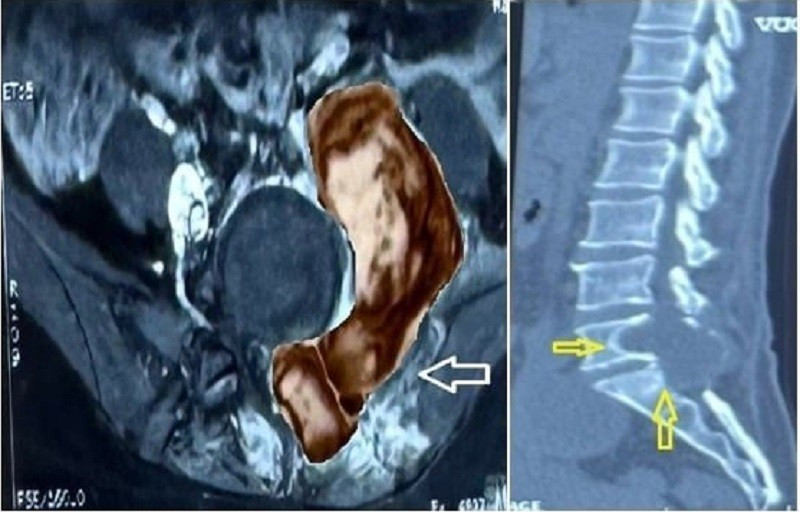

Bác sĩ xác định vị trí khối u trên hình ảnh kiểm tra (ảnh: BVCC)

Qua kết quả chẩn đoán hình ảnh, bác sĩ phát hiện một khối u lớn hình “quả tạ” ở vùng cột sống (L5-S1). Khối u đã xâm lấn cả vùng cơ thân sống, cánh chậu và vùng phúc mạc. Đây là vị trí trùng với vết mổ cũ của ca phẫu thuật bệnh nhân từng được phẫu thuật u sợi thần kinh dạng lành tính 13 năm trước.

Qua hình ảnh kiểm tra và kết quả xét nghiệm, các bác sĩ nhận định đây là khối u tái phát, nghi ngờ ác tính do kích thước và hình thái bất thường. Sau hội chẩn, ê kíp đã chỉ định thực hiện phẫu thuật loại bỏ khối u cho người bệnh.